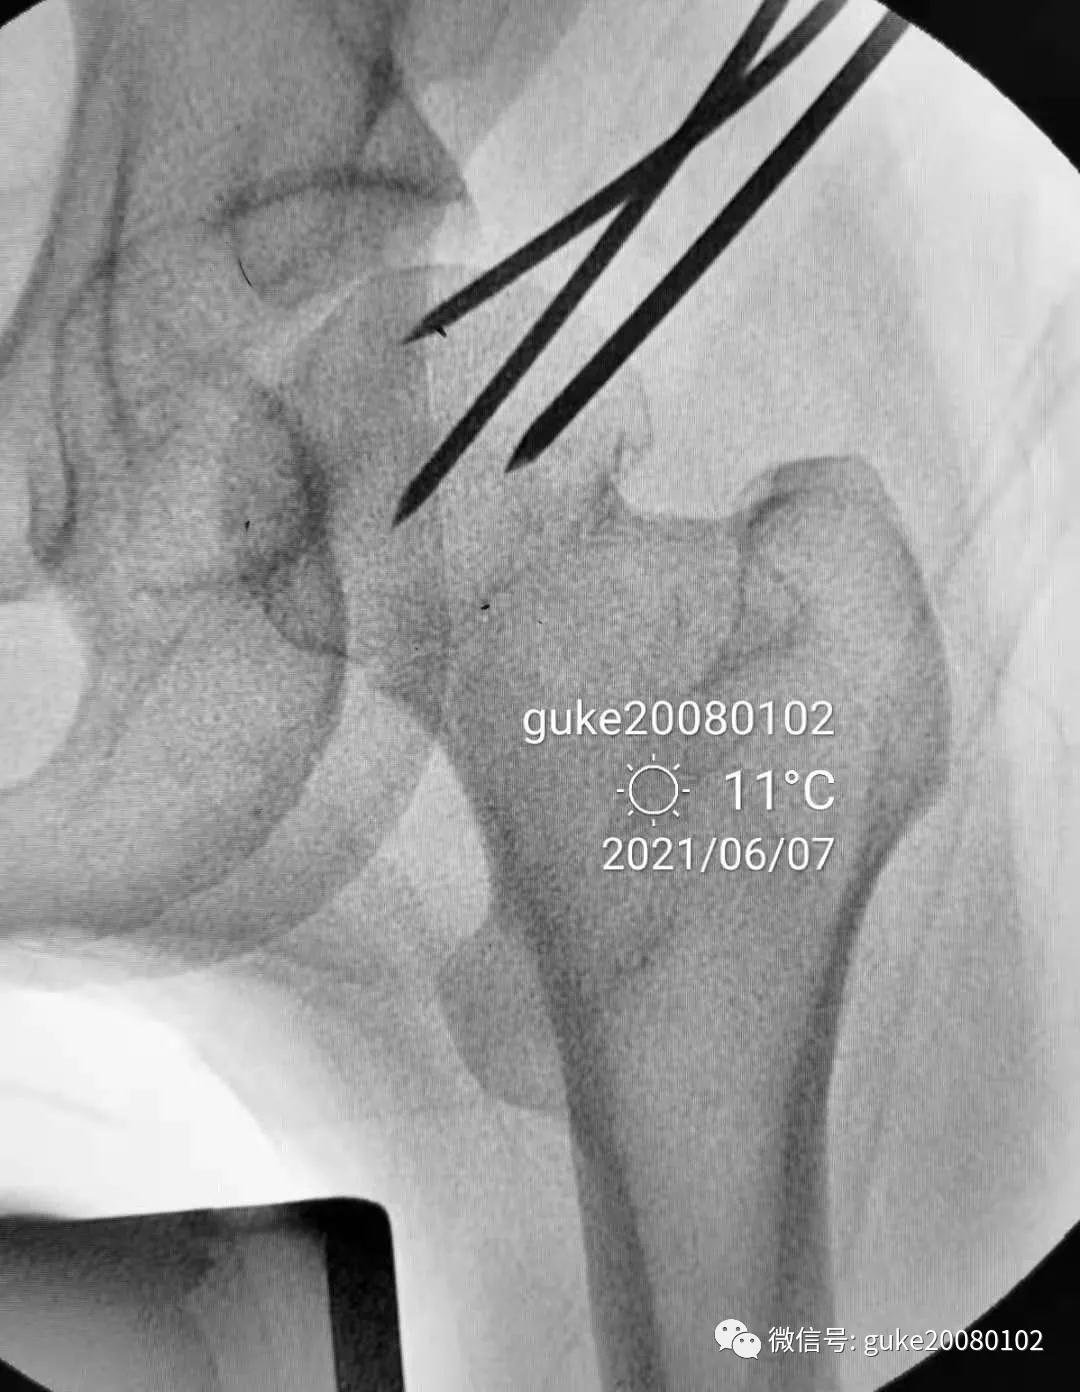

1.顺导针切开皮肤后,空心钻大转子外侧壁开口。

2.拧入三枚直径7.3mm空心钉,并逐步加压,稳定骨折断端。

最后透视: